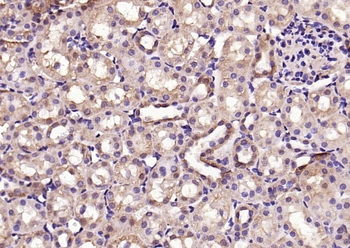

50 μl, 100 μlPhospho-Smad3 (Thr179) Rabbit Polyclonal Antibody [orb313112]

FC, ICC, IF, IHC-Fr, IHC-P

Bovine, Canine, Equine, Porcine, Sheep

Human, Mouse, Rat

Rabbit

Polyclonal

Unconjugated

100 μl, 200 μl, 50 μlSMAD7 Rabbit Polyclonal Antibody [orb500819]